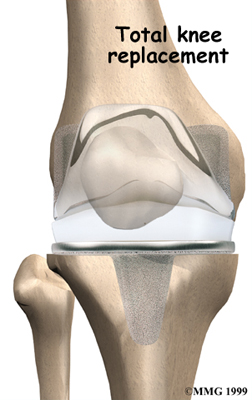

Artificial Knee Replacement

An artificial knee replacement is the ultimate solution for advanced knee OA.

Surgeons prefer not to put a new knee joint in patients younger than 60. This is because younger patients are generally more active and might put too much stress on the joint, causing it to loosen or even crack. A revision surgery to replace a damaged prosthesis is harder to do, has more possible complications, and is usually less successful than a first-time joint replacement surgery.

Related Document: FYZICAL Lakeway's Guide to Artificial Joint Replacement of the Knee